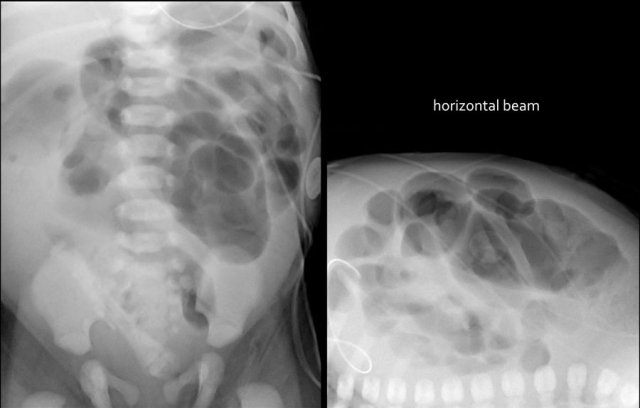

The images show a typical case of NEC with pneumatosis intestinalis.

On the horizontal beam image there is no sign of free air.